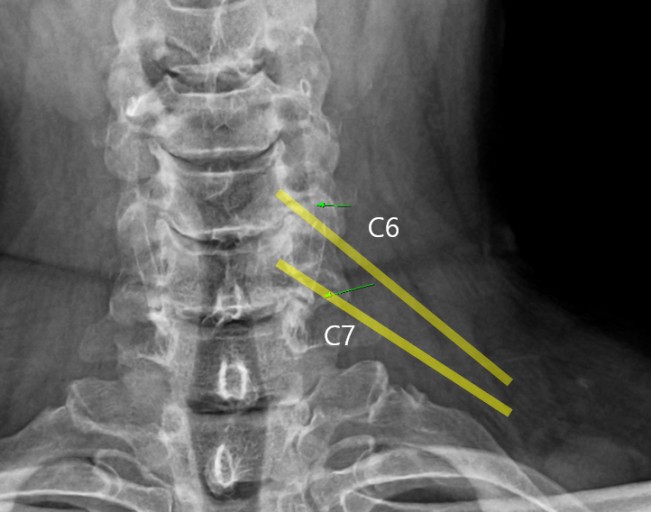

목디스크(경추 추간판 탈출증)는 경추(목뼈) 사이의 디스크가 탈출하거나 변형되어 신경을 압박하는 질환입니다. 이로 인해 다양한 증상이 나타날 수 있으며, 아래에 10가지를 아주 자세히 설명드립니다.